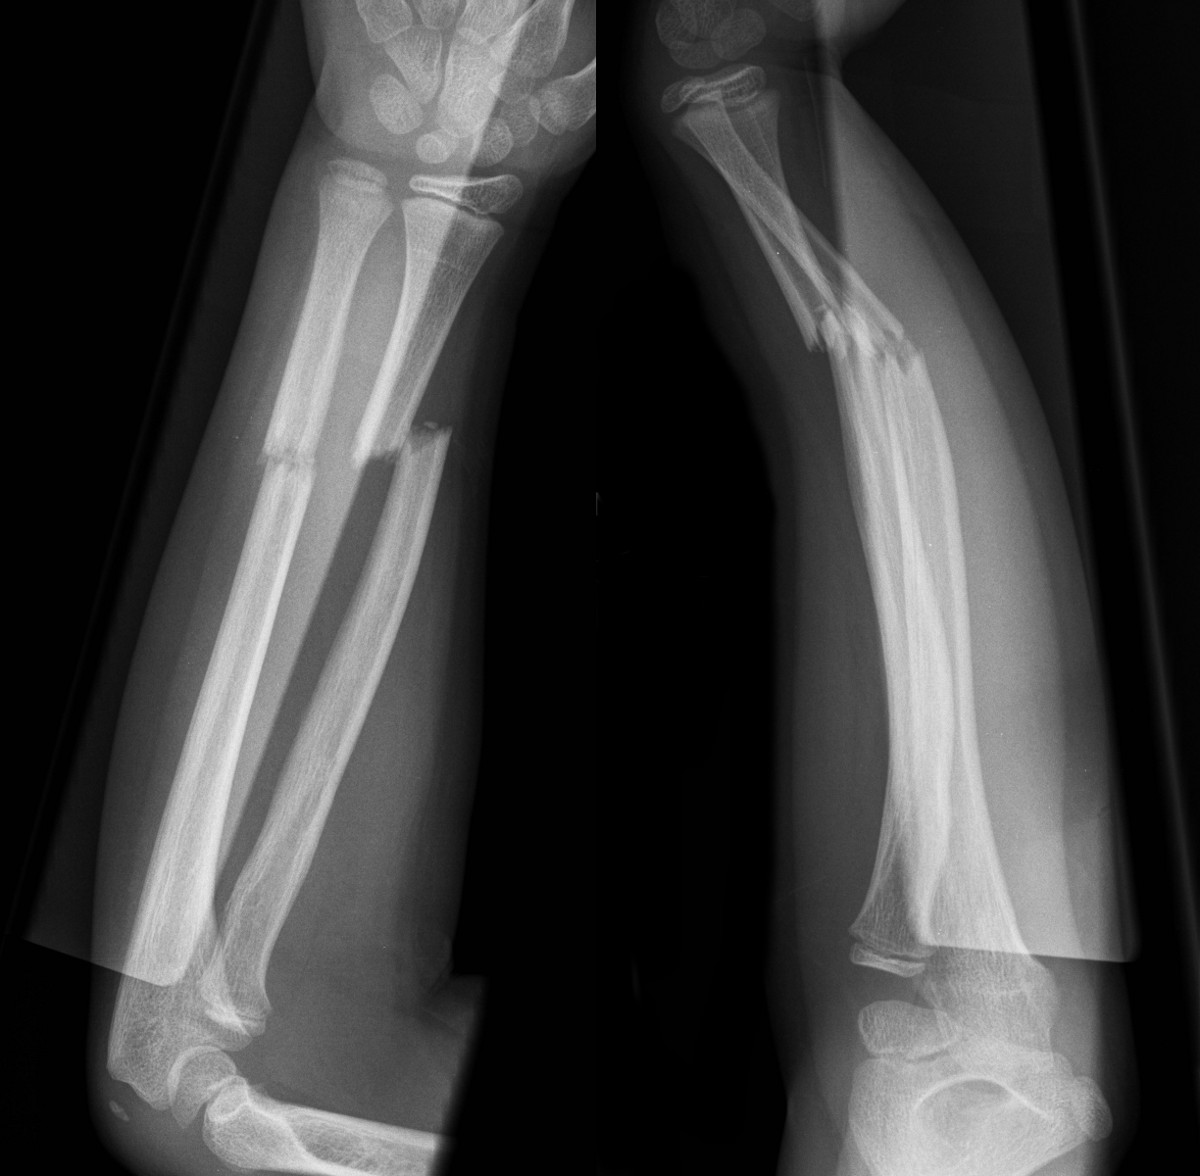

Plastic deformity of radius and ulna with volar tilt (left)

Greenstick fracture of radius shaft with 20 degrees of dorsal angulation and minimally displaced ulna fracture (right)

Transverse fractures of radius and ulna with complete displacement of radius and significant dorsal angulation (above)